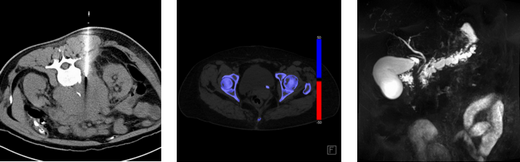

Abdominal Images

• A high-volume clinical workload offers immense learning opportunities, with more than 21,000 CT (including CT colonography, CT enterography, and CT angiography), more than 5,000 MR (including newly developed 3T pulse sequence advanced MR imaging), more than 25,000 ultrasound (including advanced vascular ultrasound and elastography), and more than 600 image-guided procedures (over the past year: liver biopsy/drainage 173, thyroid FNA 223, lymph node biopsy 159, renal biopsy 43, paracentesis 59, abdominal abscess drainage in excess of 200) in this section per year

• Rotations include 12 weeks of Body CT, 12 weeks of Body MR, eight weeks of Body Procedures, eight weeks of ultrasound, four weeks of GI/GU/Fluoroscopy, four weeks of PET, and four weeks of an elective